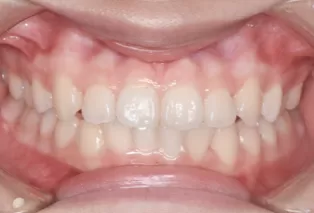

Intraoral photos